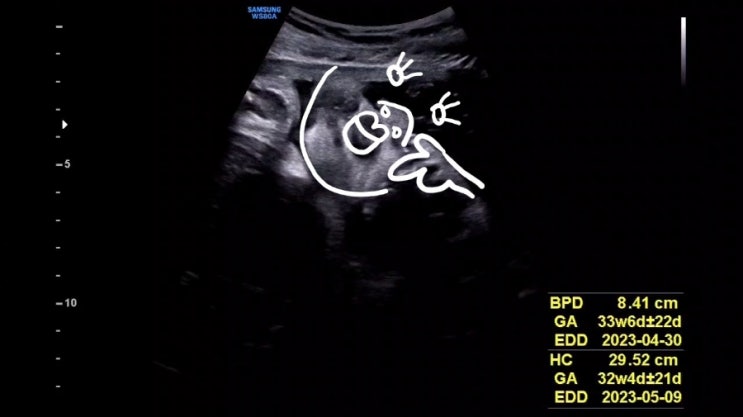

[임신했다는 얘기] 10개월 간의 소회. (엄청 긴)일기/초음파/태동

임신테스트기로 임신을 확인한 2022년 8월부터 임신 10개월 간 써 내려간 생각들 난 10달 동안 꽤나 무뚝뚝...